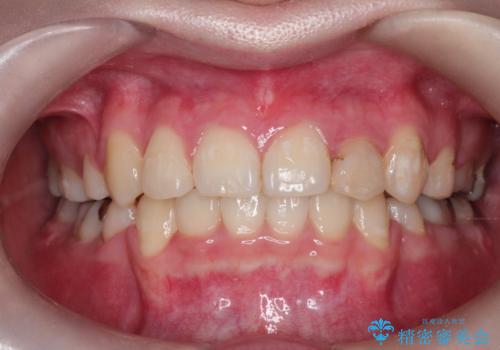

【モニター】犬歯のクロスバイトを目立たないワイヤー装置で